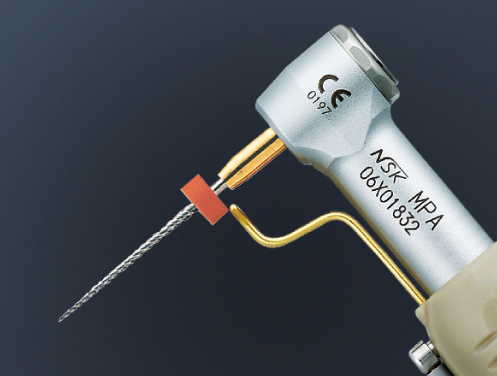

Cordless Endodontic Handpiece with Torque Control and Auto Reverse

Slim head and neck assures higher visibility.

Suitable for use with most major brands of Ni-Ti files

MPA and MPAS heads are equipped with built in probe ring which enable to use your Apex locator with the ENDO-MATE TC2 system. By combining an Apex Locator with NSK ENDO-MATE TC2, clinicians will be able to perform more accurate root canal preparations. All contra angle heads are autoclavable up to 135°C.